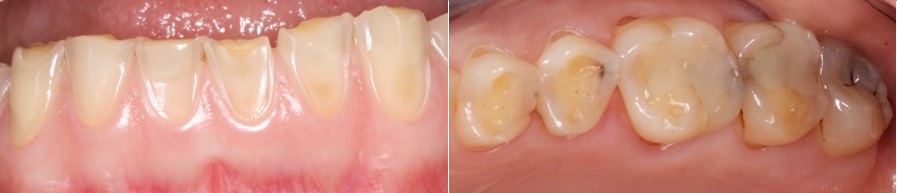

Στην εικόνα που ακολουθεί βλέπουμε τα επιπεδωμένα δόντια, και την απώλεια του σχήματος τους που είναι εμφανή τόσο στο χαμόγελο όσο και στην ενδοστοματική εικόνα δεξιά.

Σημαντική είναι και η φθορά στις μασητικές επιφάνειες των δοντιών που απεικονίζονται στις φωτογραφίες που ακολουθούν.

Όλα τα δόντια έχουν χάσει την μασητική μορφολογία τους, εκτός από την μεταλλοκεραμική γέφυρα στην κάτω γνάθο.

Τα σφραγίσματα και οι προσθετικές εργασίες δεν διαβρώνονται από τα οξέα και έτσι οι παλιές προσθετικές εργασίες ξεχωρίζουν στο στόμα, όπως φαίνεται χαρακτηριστικά στην φωτογραφία των δοντιών της κάτω γνάθου, δεξιά.

Πολύ εντυπωσιακή είναι και η εικόνα των κάτω προσθίων δοντιών που απεικονίζονται στην φωτογραφία που ακολουθεί, αριστερά.

Σε κάθε ένα από τα πρόσθια δόντια, βλέπουμε μια μικρή υπολειπόμενη ποσότητα αδαμαντίνης πολύ κοντά στα ούλα. Παρομοίως στα πίσω δόντια βλέπουμε την αδαμαντίνη που έχει μείνει περιφερικά στην μασητική επιφάνεια των προγομφίων.